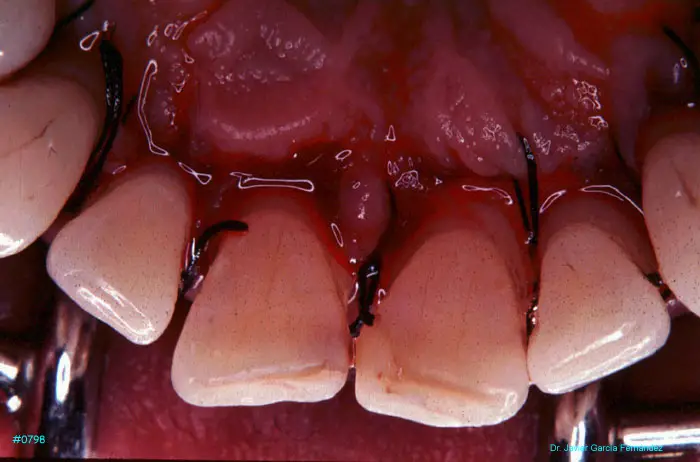

Atlas of Surgical Techniques in Periodontics. Chapter III. Atlas de Técnicas Quirúrgicas en Periodoncia